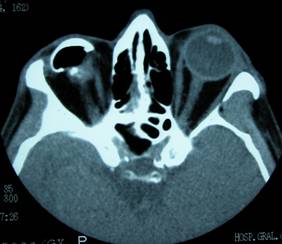

By anophthalmic we refer to the orbital cavity resulting from extraction of the eyeball either by evisceration or enucleation.

In cases of exenteration, we remove all the eyeball and adjacent orbital structures and therefore this also acts as anophthalmic cavity, although in this case complications are of another type.